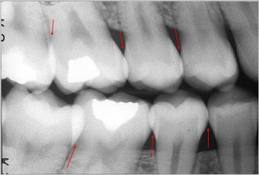

Radiografía de aleta mordible

(Bite-Wing)

|

La técnica tiene ventajas

con respecto a la radiografía periapical, debido que

reduce el tiempo de exposición a la radiación y disminuye

los costos y honorarios.

Técnica:

La cabeza del paciente se

coloca de manera que el plano de oclusión quede paralelo al del

piso. El rayo central se dirige al punto de contacto de los

dientes superiores con los dientes inferiores y paralelo a sus

superficies proximales, con el tubo formando un ángulo de 5 a

10º por encima del plano horizontal.

Ver figura 5. Para los dientes posteriores es

deseable tomar dos vistas de cada lado:

-

una en la que la película

se coloca más atrás para incluir el espacio inter-proximal

entre el segundo y el tercer molar,

-

y la otra lo bastante adelante

como para tomar la cara distal del canino. Solo necesita cuatro

películas para el diagnóstico de caries en todos los sectores

posteriores.

-

Cuando el tercer molar se

encuentra en proceso de erupción y se observa solo una parte de la

corona clínica a la inspección visual, es de utilidad diagnóstica

general, una imagen de una radiografía periapical de esa pieza

dental en particular.

|

Figura 5 |